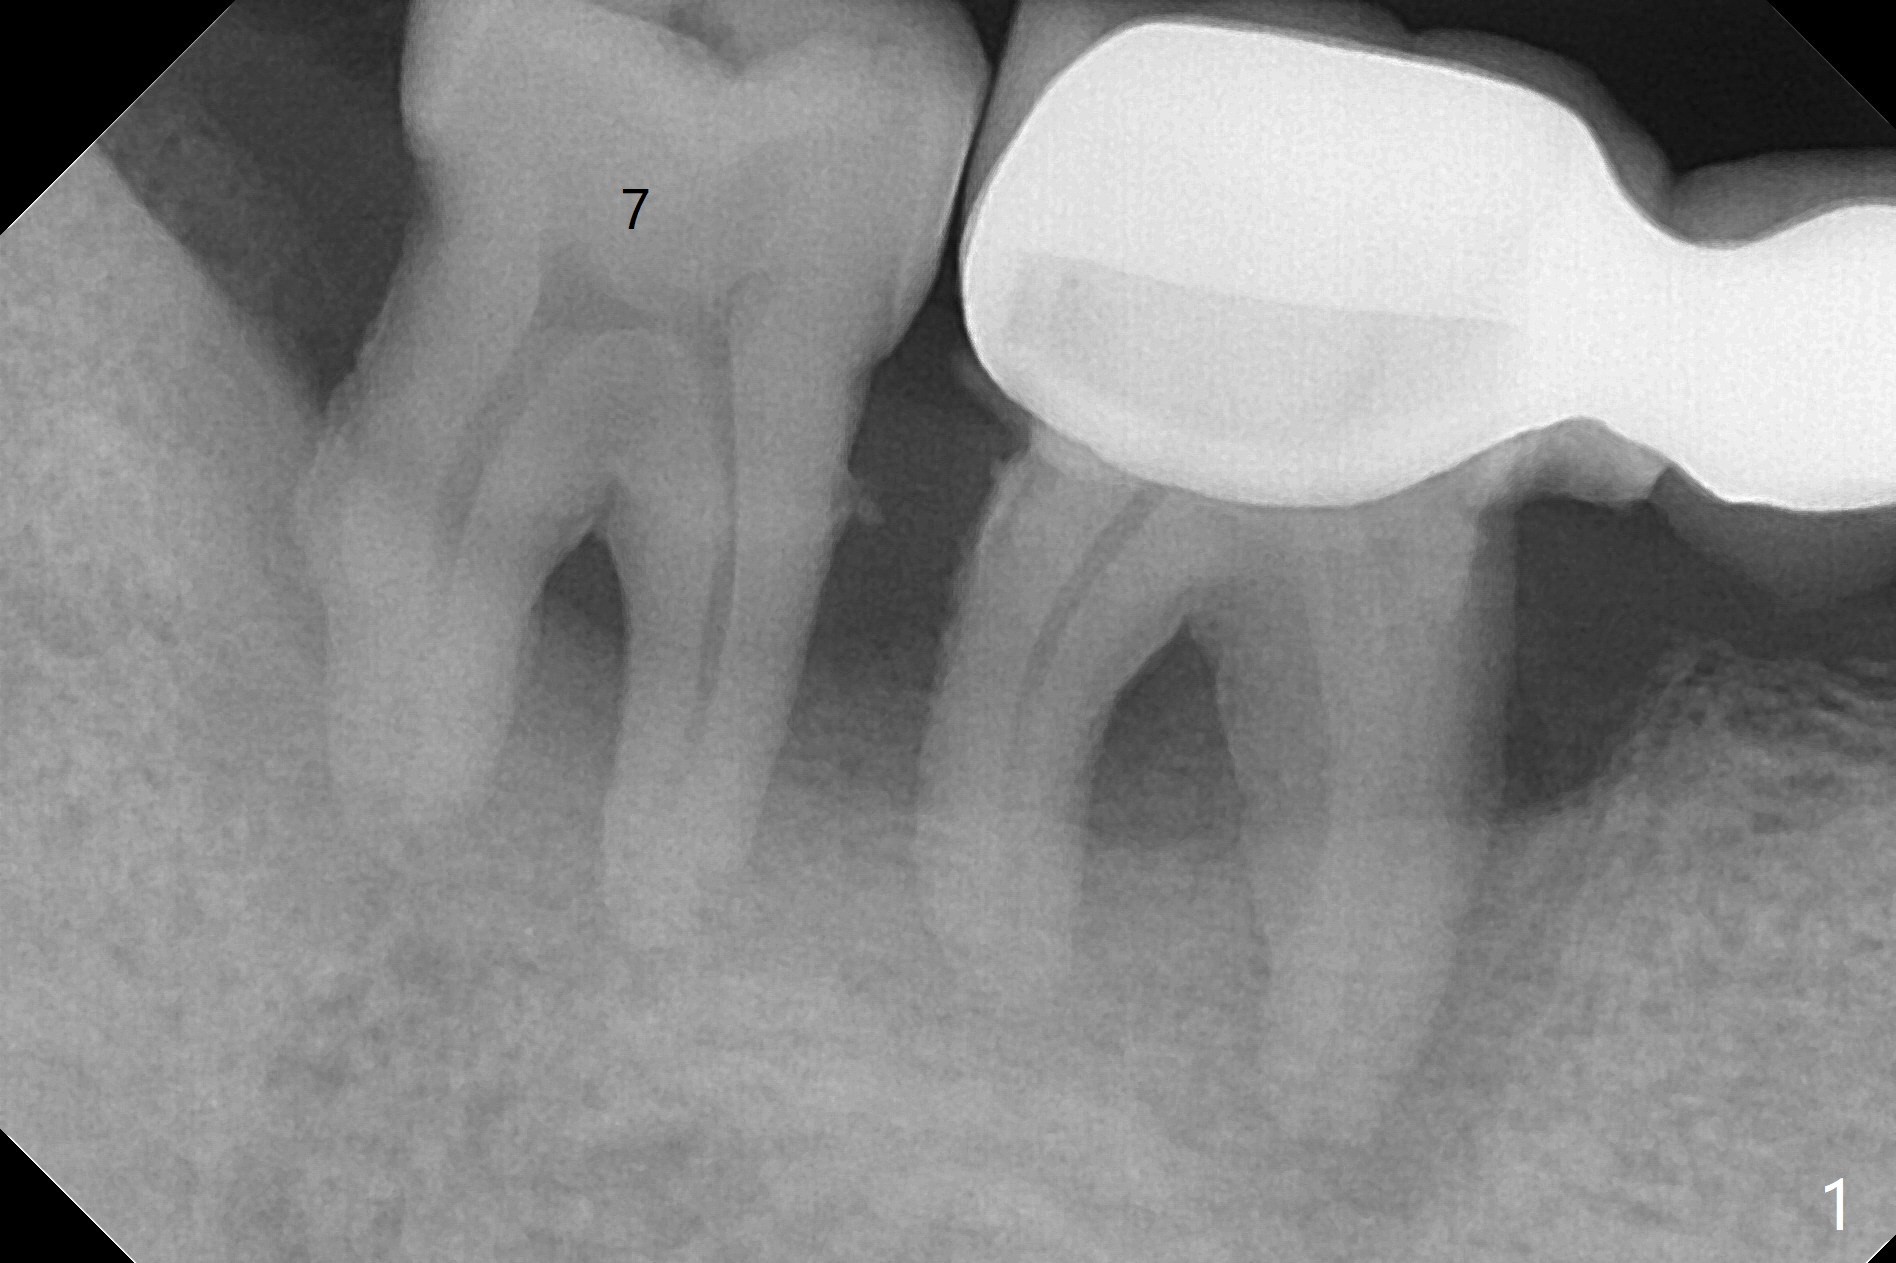

44岁男,吸烟,一天半包,严重牙周病,左上托牙,右下7骨质吸收(图一),松动,影响吃饭,起初他不同意植骨,后来改变主意。拔牙时发现牙龈袋特别深,清创(包括近中)后,放置许多骨粉(皮质),骨高度至少增加5-6毫米(图二)。不可吸收膜,PTFE缝线。如果以后6号牙需要拔除(图三黑色),为了维持龈乳头,牙间牙龈下部分应该切除(图四橘黄色),空间由骨粉充填(图五红色圆圈),以便重新建立牙间牙槽嵴。